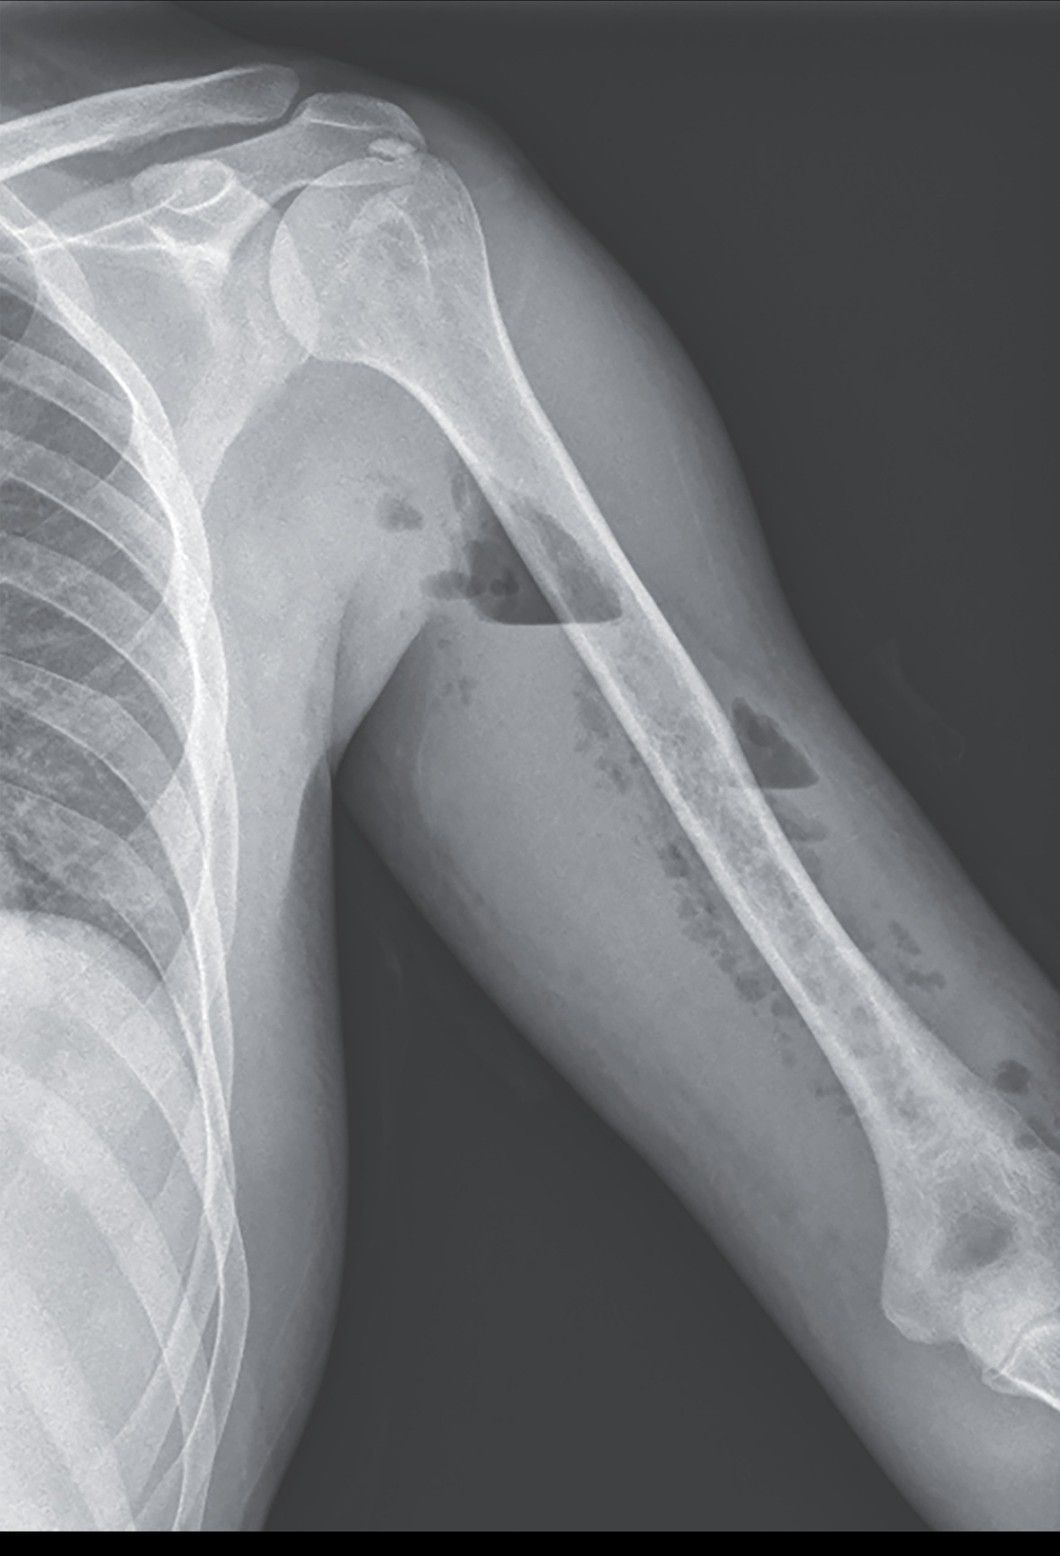

A 37-year-old man presented to the emergency department with a 1-week history of pain and swelling in the left upper arm that had started after blunt trauma to the arm during a soccer practice. He had a history of opioid use disorder, which had been treated with buprenorphine. He reported no intravenous drug use during the past 2 years. The heart rate was 120 beats per minute, the blood pressure 96/54 mm Hg, and the body temperature 37.9°C. Examination of the left upper arm was notable for swelling, tenderness, and crepitus. The overlying skin was red and warm to the touch. A radiograph of the upper arm showed radiolucent areas with air–fluid levels in deep tissue. Subsequent computed tomography of the upper arm revealed pockets of gas in the muscles of the extensor compartment. Owing to concern about necrotizing myositis, emergency surgical débridement was performed, and the diagnosis of necrotizing myositis was confirmed. In patients with necrotizing myositis, plain radiographs may show only soft-tissue edema, unlike the radiographic findings in this case. Clinicians should have a high index of suspicion for this life-threatening condition in patients with focal, progressively worsening muscle pain and systemic symptoms. A second débridement was performed 48 hours after the initial surgery. After 3 weeks of broad-spectrum antimicrobial therapy to treat a polymicrobial infection, the patient’s condition improved, and he regained function of his arm.